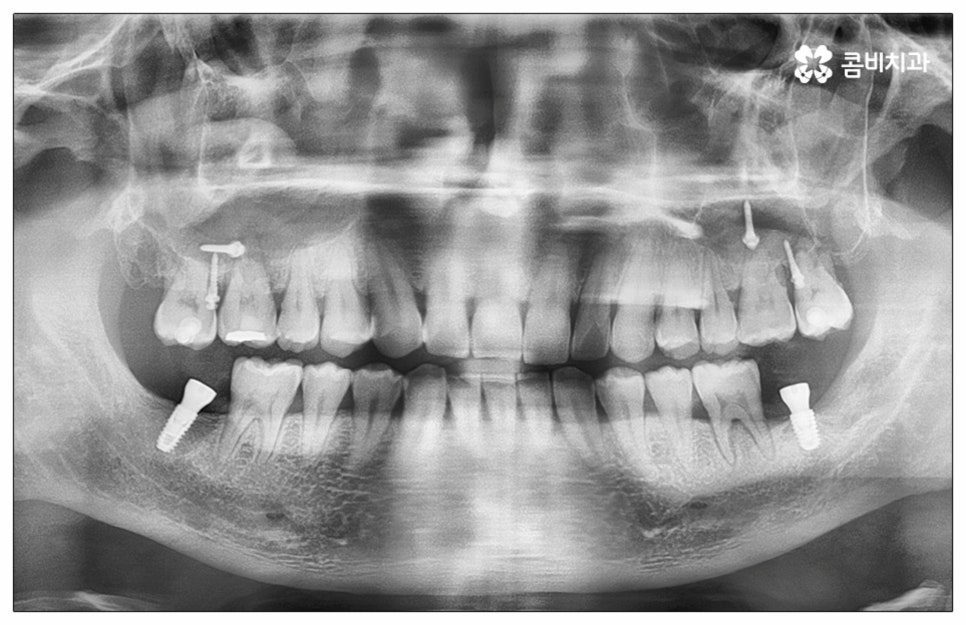

예전에는 이런 상황에서 틀니를 많이 이용하였으나 저작력 회복이 본래 자신의 치아 대비 20~30% 정도 밖에 되지 않고 잦은 탈락 위험 및 이물감, 잇몸을 눌러 장기적으로 잇몸뼈가 내려앉을 수 있다는 점 등 여러 가지 불편함이 있어 요즘은 임플란트 시술을 선호하시는 분들이 더 많아지고 있어요. 임플란트란 인체에 무해하며 잇몸뼈와 잘 결합하는 인공 치근을 잇몸뼈에 직접 식립하고 그 위로 기둥이 되는 중간 지대주와 치아 머리가 되는 크라운 보철물을 연결하여 인공 치아를 만들어 주는 시술을 말하는데, 자연 치아의 80% 정도 저작력 회복이 가능하기 때문에 식사를 할 때 음식을 크게 가리지 않아도 된다는 점 그리고 심미적으로 봤을 때 주변 치아와 자연스럽게 어우러진다는 점 때문에 각광을 받고 있습니다. 게다가 건강 보험 가입자이면서 만 65세 이상 부분 무치악 환자라면 평생 임플란트 2개까지 보험 적용을 받아 비용 부담을 줄일 수 있기 때문에 더욱 더 수요가 늘어나 이제는 치아 상실에 대체하는 대표적인 방법으로 임플란트 시술이 꼽히고 있는데요.

많이 대중화 되었다고 해도 임플란트 수술 자체가 술자의 숙련도에 크게 영향을 받는 복잡하고 고난도의 진료인 것은 틀림이 없기 때문에 담당 의료진이 해당 분야 임상 경험이 풍부한지, 뛰어난 기술력과 노하우를 가지고 있는지 꼼꼼하게 체크해 보실 필요가 있어요. 특히 노년층의 경우 당뇨, 고혈압 등 만성 질환을 앓고 있는 경우가 많아 혹시 상시 복용하고 있는 약이 있는지, 현재 환자 개개인의 상태는 어떤지, 사전 처치가 필요한 부분은 없는지 등등 수술 조건을 좀 더 까다롭게 평가한 후 환자분들과 이에 대해 충분히 상담하고 맞춤형 치료 계획을 세워 진행해야 하며 이를 위해 3D CT 와 같은 디지털 검진 장비를 통해 구강 내부 구조를 면밀하게 살피고 방대한 임상 데이터를 축적한 정품 임플란트 재료를 이용하여 연령이나 회복 정도를 살펴보면서 체력적 부담을 줄이는 방향으로 무리하지 않게 식립하는 것이 무엇보다 중요하다고 할 수 있습니다.

이때 추가 수술은 비급여 항목으로 건강보험임플란트 대상에서 제외되니 이에 대해서도 꼼꼼하게 살펴보시고 정밀 검진 후 담당 의료진과 자신의 상황에 대해서 충분하게 상담해 보시길 권유드리고 있습니다. 추가 수술의 대표적인 예로는 뼈이식 수술이 있는데요. 이것은 임플란트를 식립할 때 바탕이 되는 잇몸뼈의 높이나 폭, 밀도 등이 부족하다면 먼저 이를 보충해 주고 나서 임플란트를 심어주는 과정을 의미하며 같은 이유로 식립 성공률이나 장기적인 안정성을 높이기 위해 꼭 필요한 사전 처치, 즉 상악동 거상술 및 치주 질환 관련 수술 등을 먼저 해야 한다면 이 역시 추가 수술의 범주로 들어가니 자신의 상황에 대해서 상세하게 알아보실 필요가 있어요.